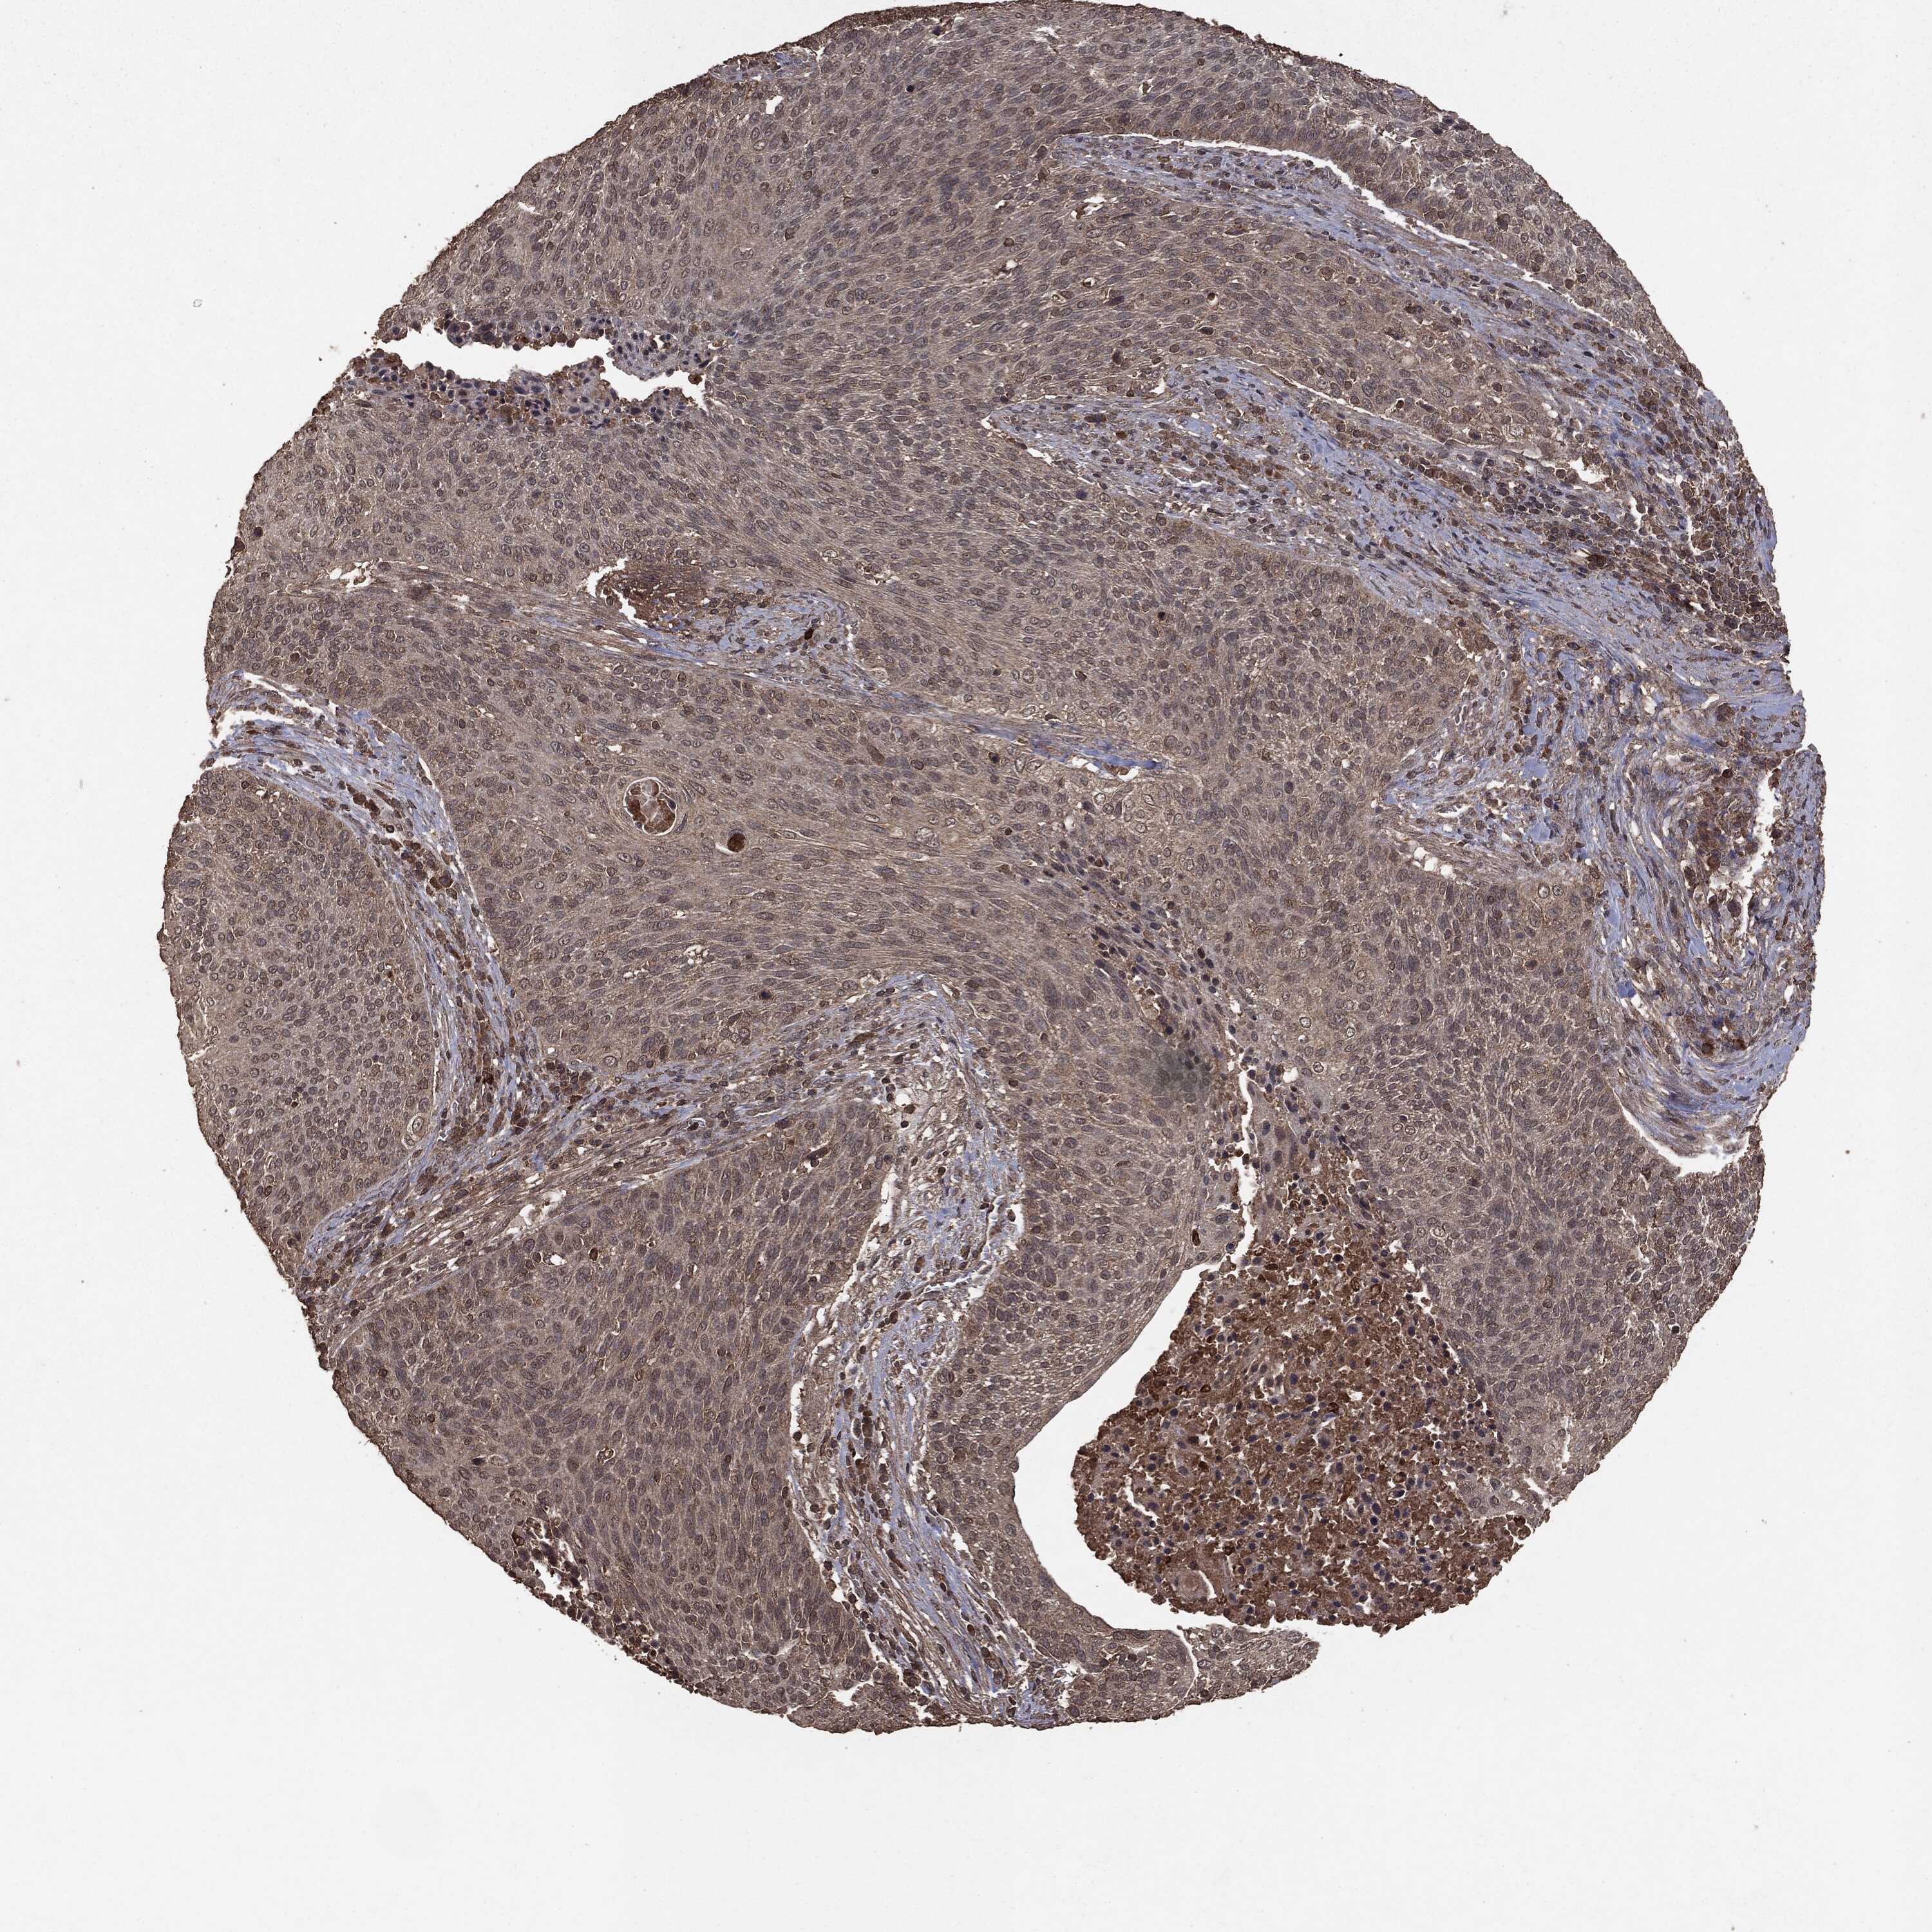

CERVICAL CANCER - Protein expressioni

A mouse-over function shows sample information and annotation data. Click on an image to view it in a full screen mode. Samples can be filtered based on level of antibody staining by selecting one or several of the following categories: high, medium, low and not detected. The assay and annotation is described here.

Note that samples used for immunohistochemistry by the Human Protein Atlas do not correspond to samples in the TCGA dataset.

Antibody stainingi

Antibody staining in the annotated cell types in the current human tissue is reported as not detected, low, medium, or high, based on conventional immunohistochemistry profiling in selected tissues. This score is based on the combination of the staining intensity and fraction of stained cells.

Each image is clickable and will lead to virtual microscopy that enables deeper exploration of all samples and also displays staining intensity scores, fraction scores and subcellular localization as well as patient and tissue information for each sample.

HPA008467

HPA041113

CAB040571

CAB080149

CAB080151

CAB080152

Staining

High

Medium

Low

Not detected

Intensity

Strong

Moderate

Weak

Negative

Quantity

>75%

75%-25%

<25%

None

Location

Nuclear

Cytoplasmic/membranous

Cytoplasmic/membranous,nuclear

Squamous cell carcinoma, NOS

Adenocarcinoma, NOS